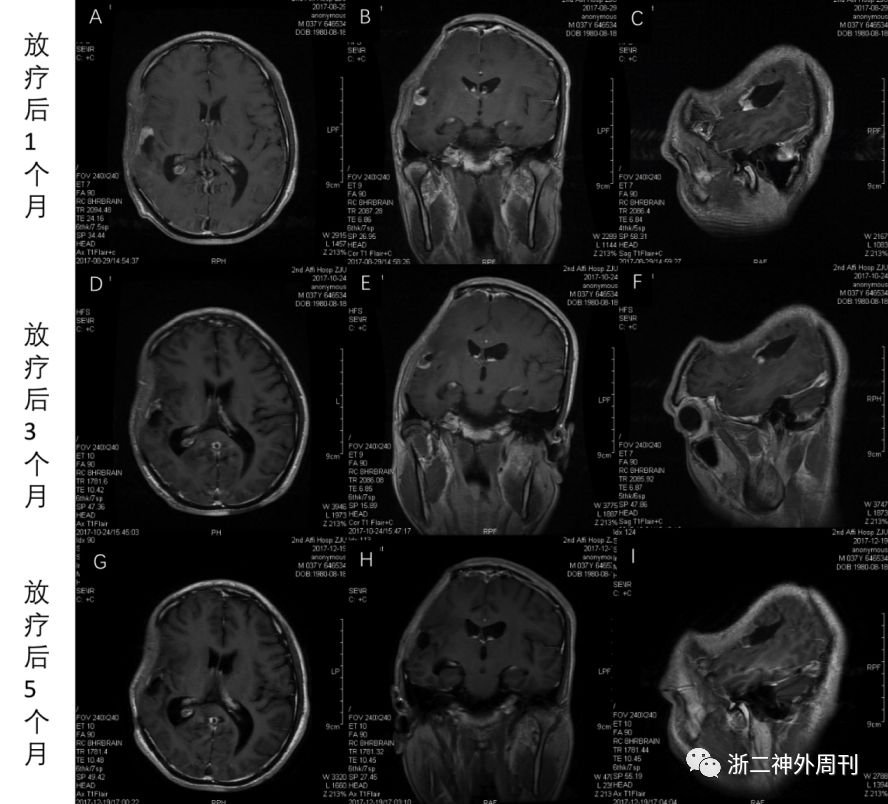

2017-06-20开始行放疗:右颞叶残留灶及周围高危区PTV1 48Gy/24F + PGTV 10Gy/5F,泰道每日75mg/m2 同步化疗。放疗结束后予泰道5/28方案化疗6周期(第1周期150 mg/m2/日,第2-6周期200 mg/m2/日)。放疗结束后头颅MRI复查无明显变化,至放疗后1月开始病灶缩小,放疗后3月明显缩小,放疗后5月可见病灶已消失(图3,4)

图4.放疗后1月头颅MRI(A-C);放疗后3月头颅MRI示残留病灶开始缩小(D-F);放疗后5月头颅MRI示残留病灶基本消失(G-I)